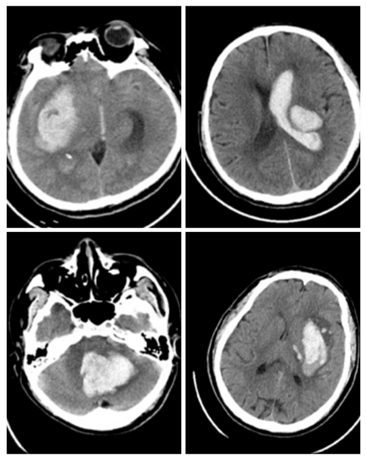

腦出血患者的CT片,中間白色區(qū)域?yàn)槌鲅?/em>